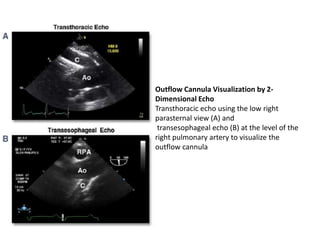

Outflow Cannula Visualization by 2-

Dimensional Echo

Transthoracic echo using the low right

parasternal view (A) and

transesophageal echo (B) at the level of the

right pulmonary artery to visualize the

outflow cannula

• Other complicationsinclude kinking, thrombus, or endocarditis at the outflow cannula–ascending aorta anastomotic site. • A modified parasternal transthoracic echo approach can often follow the course of the outlet conduit up the anterior chest to the level of the aortic anastomosis as well, serving as a routine LVAD view. • Transesophageal echo may be useful in visualizing this area from the transverse aorta level or through the level of the right pulmonary artery.

Outflow Cannula Visualizationby 2- Dimensional Echo Transthoracic echo using the low right parasternal view (A) and transesophageal echo (B) at the level of the right pulmonary artery to visualize the outflow cannula